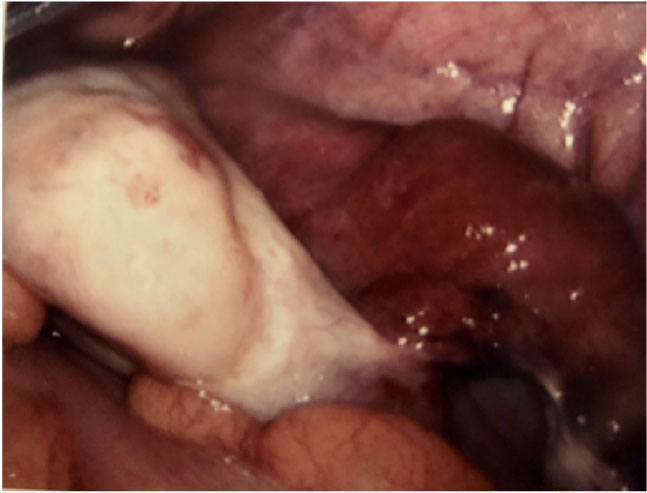

The patient's presentation raised clinical suspicion of acute appendicitis. A diagnostic laparoscopy was initiated by the general surgical team on call. Laparoscopic findings revealed an appendix with slightly increased vascular injection and a laparoscopic appendectomy was performed. A large dark blue necrotic 6 × 5 cm pelvic mass was also noted, so that the gynaecological team on-call were asked to attend. A careful examination of the mass revealed a distally dilated, twisted, necrotic right fallopian tube (Figure 1). There was no associated ipsilateral ovarian involvement (Figure 2). The contralateral Ovary, fallopian tube and the rest of the pelvis appeared normal. Untwisting failed to improve colour of the tube, so that a right salpingectomy was performed. Histopathological findings revealed a torsed dilated fallopian tube with necrosis and extensive haemorrhage. The Patient recovered uneventfully from the surgery and was discharged on the third postoperative day.

Figure 1: Intraoperative photo showing a dilated, twisted, necrotic right fallopian tube. View Figure 1